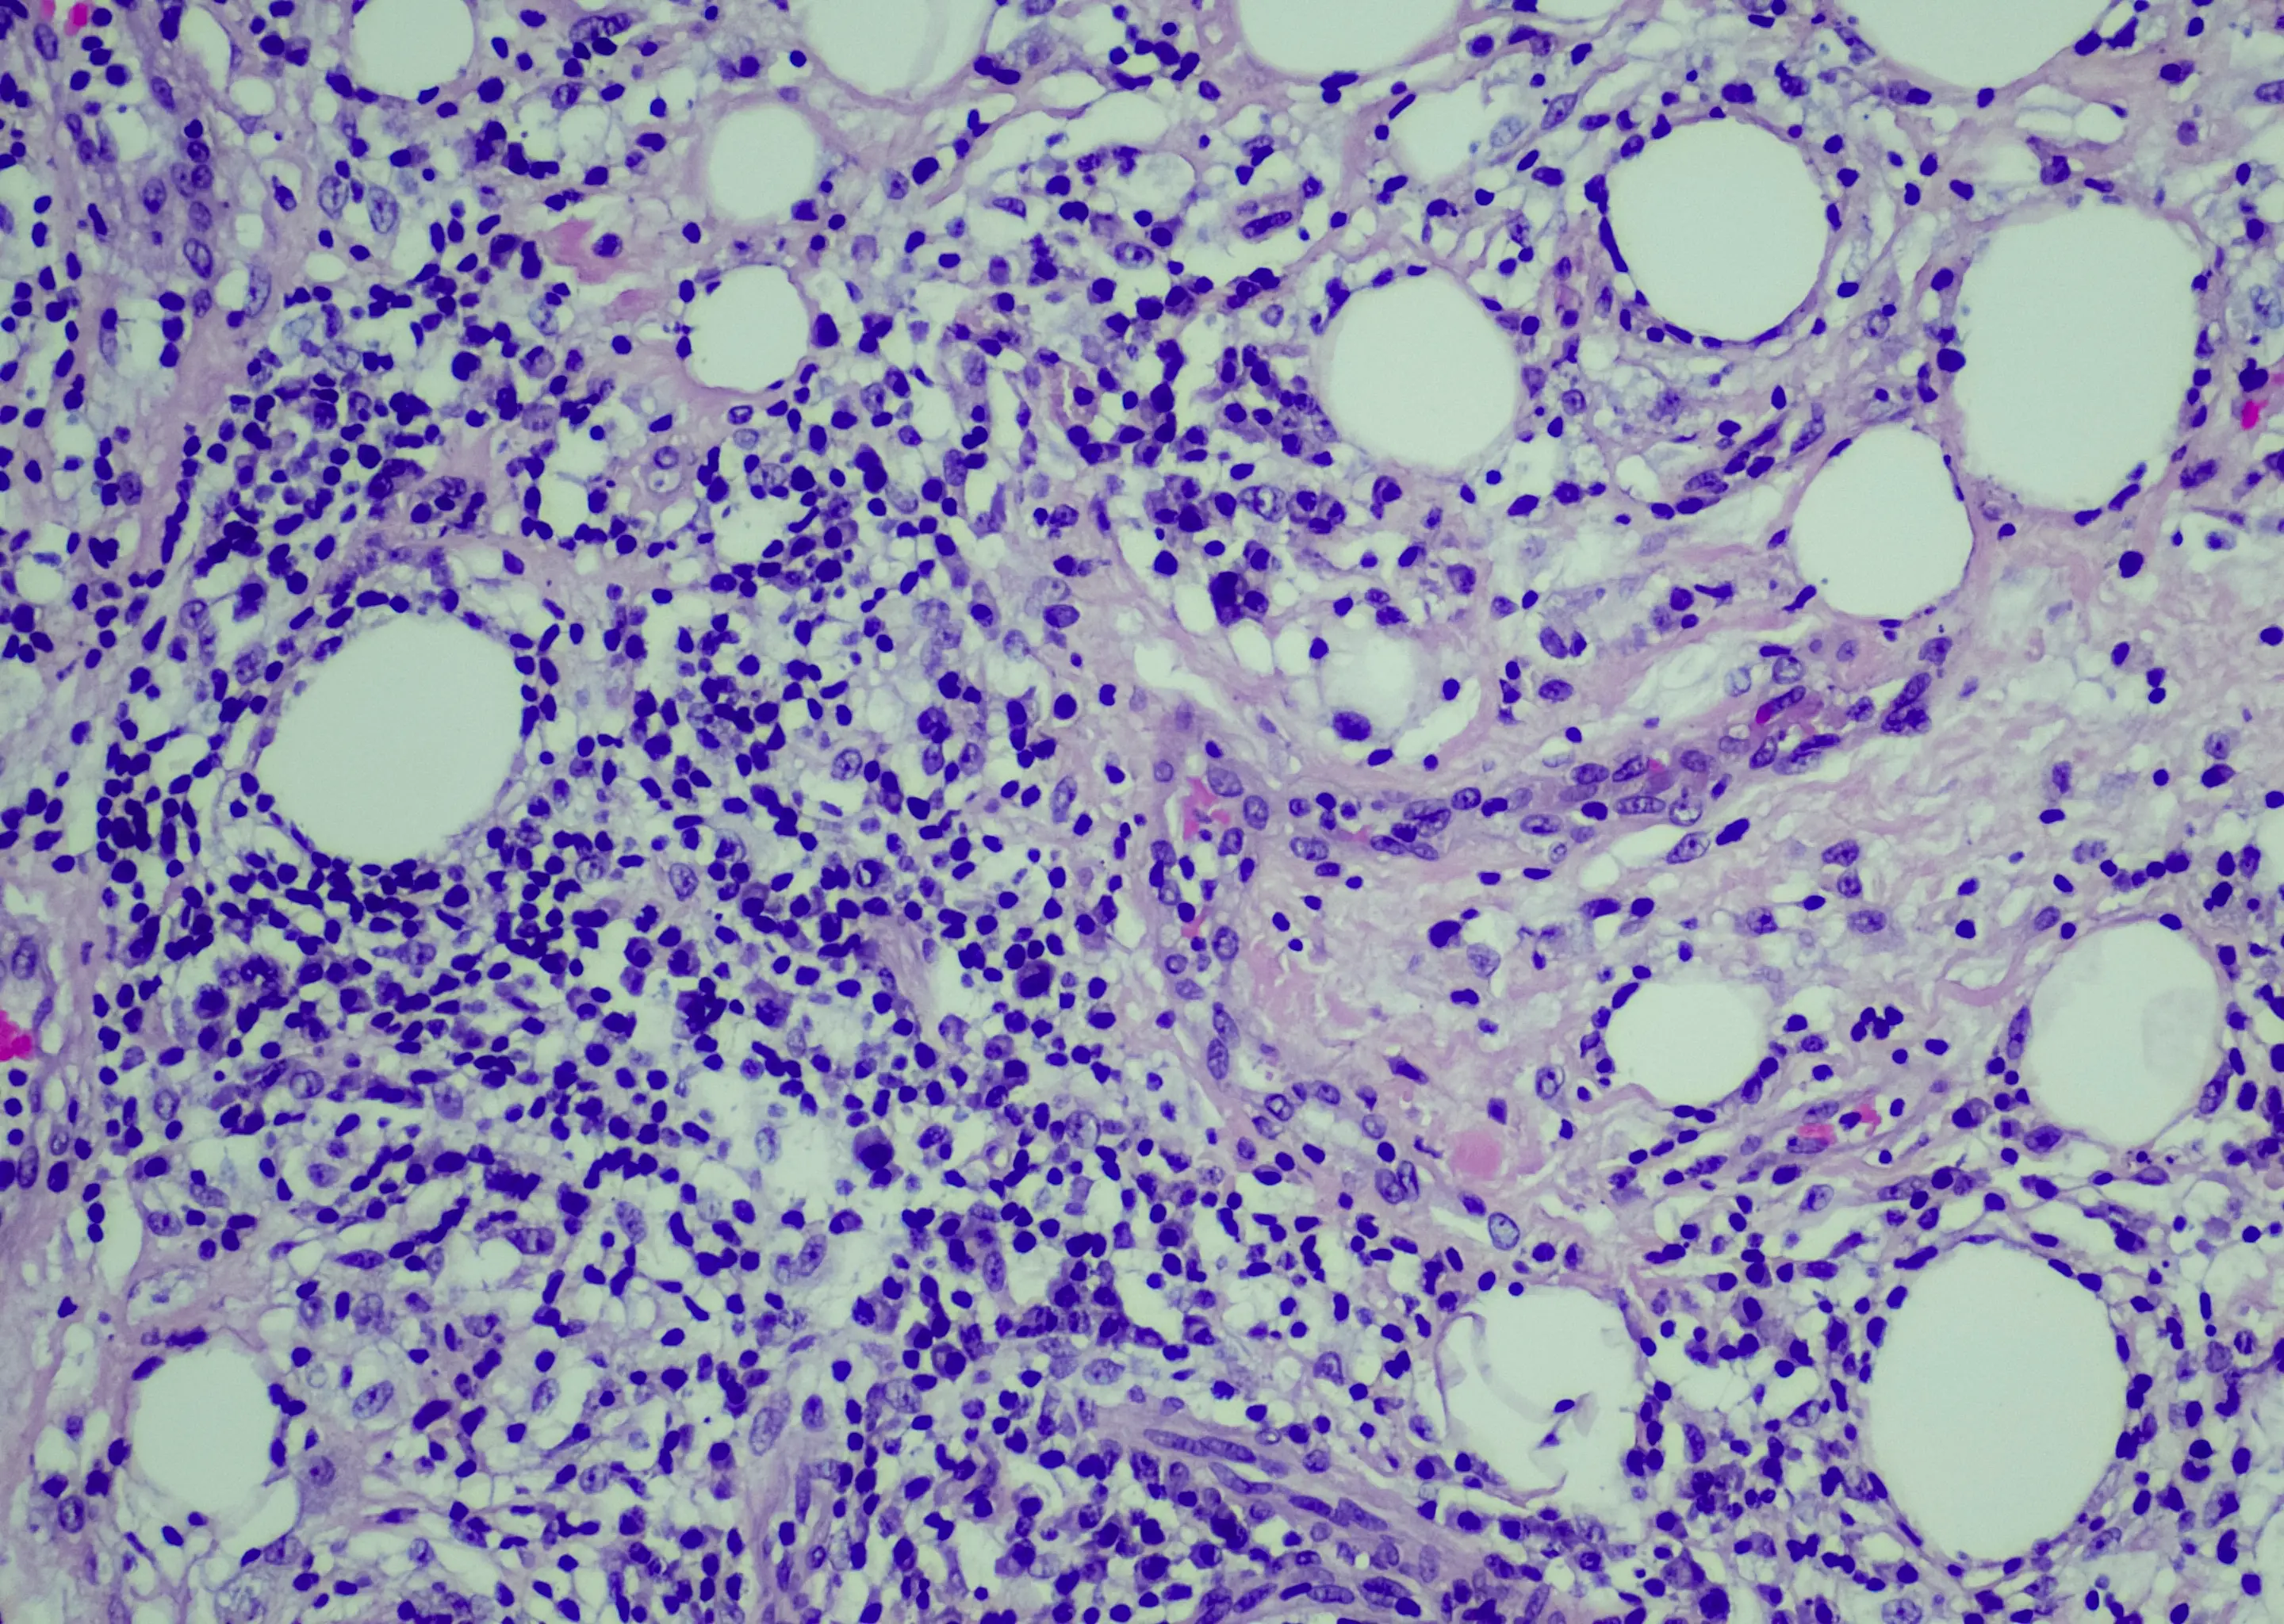

Hodgkin lymphoma is a type of lymphoma cancer that affects the lymphatic system and lymph nodes.

With this type of cancer, it begins in the white blood cells called B lymphocytes and is treated with one or a combination of treatments like ‘chemotherapy, radiation, targeted therapy, immunotherapy, bone marrow transplant, also called bone marrow stem cell transplant, and clinical trials.’

Dr Garg says a symptom of this is ‘severe, generalised itching’ that is generally worse at night.

Other symptoms include pains in the glands in your groin, armpit or neck, a temperature, sweating at night, sudden weight loss, a painless lump in your glands, or shortness of breath.